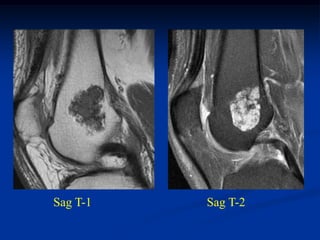

Case #632

26 year male with chondroblastoma prox tibia

Lateral view

Sagittal T-1 MRI

Sagittal T-2 MRI

Photomic